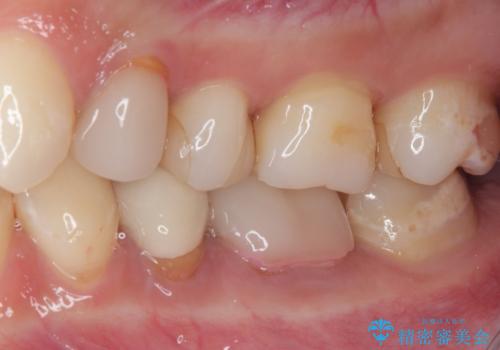

右下奥歯は既に根管治療が行われており、セラミッククラウンが装着されていました。

セラミッククラウンを壊して再度根管治療を行い、その後セラミッククラウンを装着する方法か、外科的に歯根の先端を切除し、炎症の原因である細菌を取り除き治癒を図る方法とを提案し、極力クラウンを壊さずに治療を進めたいとの希望により、歯根端切除術を行うこととしました。